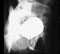

Vasogram Prostate: Examine the prostate gland and attachments to the pubis via the puboprostatic ligament. Note relation of prostate to bladder, urogenital hiatus and rectum (ampulla). Trace the course of the ejaculatory duct. In the prostatic urethra, examine the urethral crest, prostatic sinus, colliculus seminalis and note specifically the openings of the ejaculatory ducts.

Review the urethra and determine prostatic, membranous, and penile (spongy) parts.

Male urethrogram Obstructed ureter 5. Examine the external genitalia in the male. (Play movie; View images: N 351, 377, 382, 387A, 387B, 390, 398, TG 6-02, 6-25A, 6-25B, 6-31)